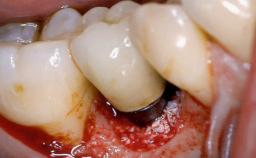

Despite anti-infective surgical treatment, some patients may experience recurrent infection and progressive bone loss requiring additional treatment. Removal of Implant Due to Recurrent Infection describes a conservative approach using an implant retrieval tool without the need for excessive bone removal or use of a trephine.

A 70-year-old female patient was referred by her general dentist to the periodontist for assessment and management of an infection associated with implant 36. The general dentist had noted suppuration on probing during examination.